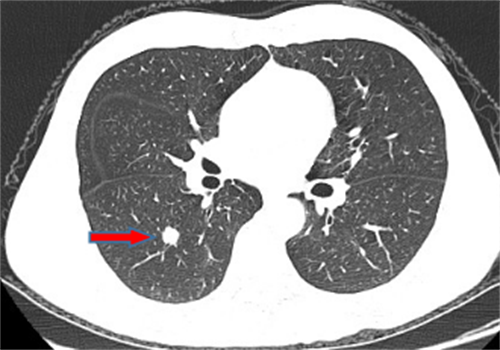

龙先生,65岁,体检发现右下肺结节,术后病理诊断肺结节为硬化性血管瘤。